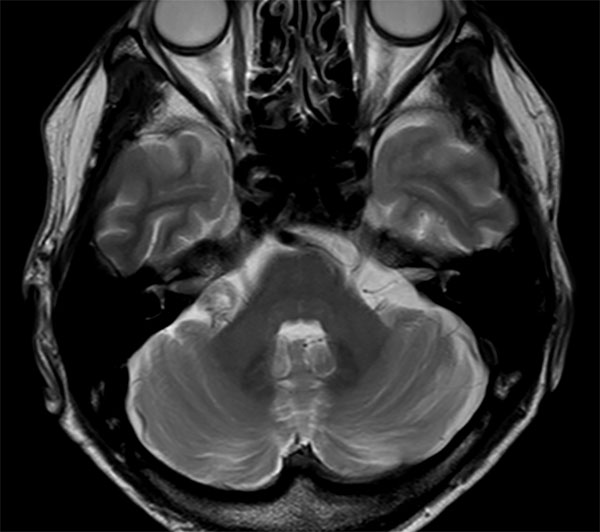

IAC – Acoustic Neuroma

Decreasing hearing of the right side. Buzzing and beating sensation in the right ear. Sometimes pain. Request for MRI of the inner ear without and with contrast agent.